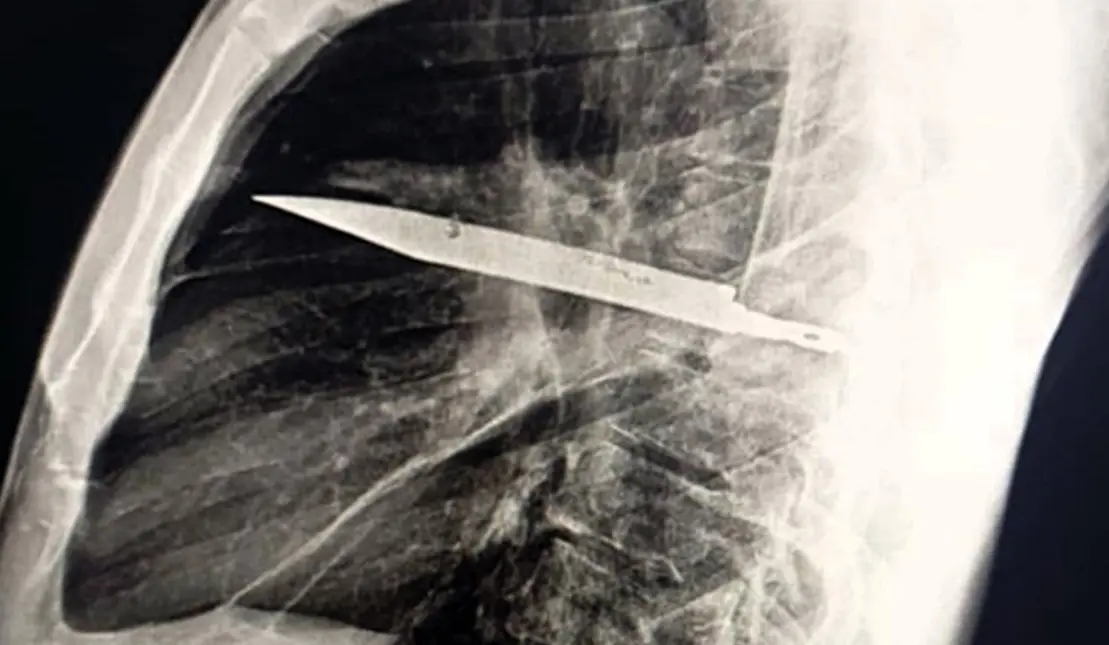

Рентгенограма виявила справжню причину незвичних симптомів: у тілі застрягло велике лезо, що пройшло через праву лопатку й дивом не зачепило життєво важливі органи.